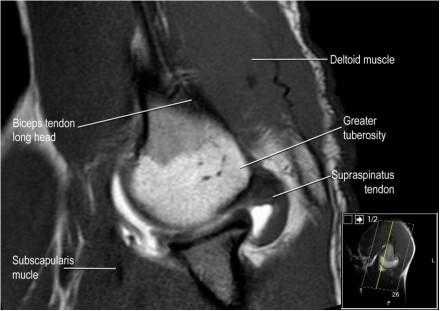

Нормальная сагиттальная анатомия и контрольный список

- обратите внимание на мышцы манжеты вращателей и поищите их атрофию

- изучите место прикрепления длинной головки двуглавой мышцы плеча к суставной губе (biceps anchor)

- обратите внимание на форму акромиона

- поищите импинджмент за счет акромиально ключичного сустава. Обратите внимание на интервал между мажетой вращателей и клювовидно-плечевой связкой (coracohumeral ligament).

- поищите повреждение подостной мышцы